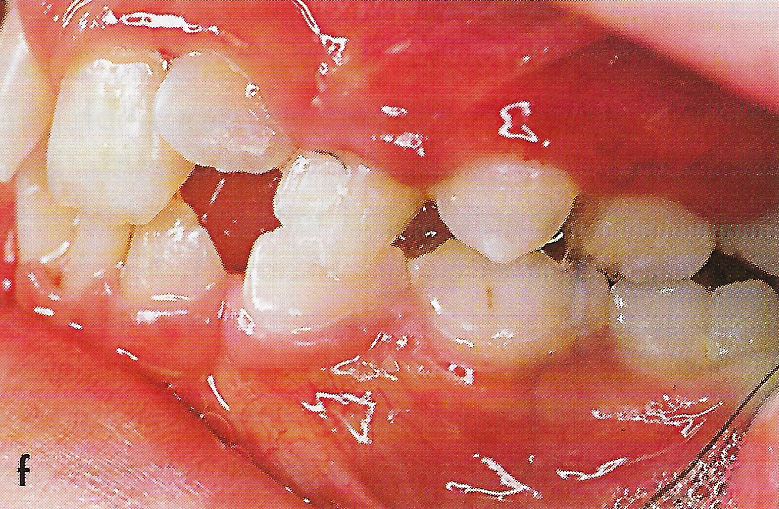

Abb. 12 a bis h Extra- und intraorale Ansicht der Patientin unmittelbar nach Entfernung der Apparaturen nach 8 ½ monatiger Protraktion des Oberkiefers. Der umgekehrte Überbiß und der Kreuzbiß sind beseitigt. Die mandibuläre Verschiebung besteht weiterhin und bedingt eine mesiale Verzahnung im linken Seitenzahngebiet. Es sind keine Zahnkippungen erkennbar. Die entzündlichen Gingivaveränderungen heilen innerhalb weniger Tage ab.

• Ankylose Abb.12c

• Ankylose Abb.12f

Die Patientin wies nach der 8 ½ monatigen Protraktionstherapie eine positive inzisale Stufe auf, der Kreuzbiß und der Mesialbiß waren korrigiert; Zahnkippungen waren nicht erkennbar (Abb. 12 a bis h).